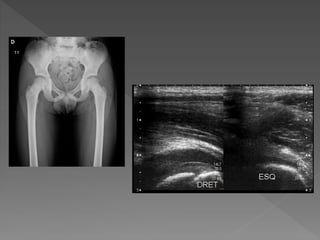

   Rx de caderas: No se observa aumento en

el espacio de articulación coxofemoral

derecha. No se observan líneas de fractura.

   Ecografía: mínimo aumento de líquido

intraarticular < 3mm, no derrame articular.